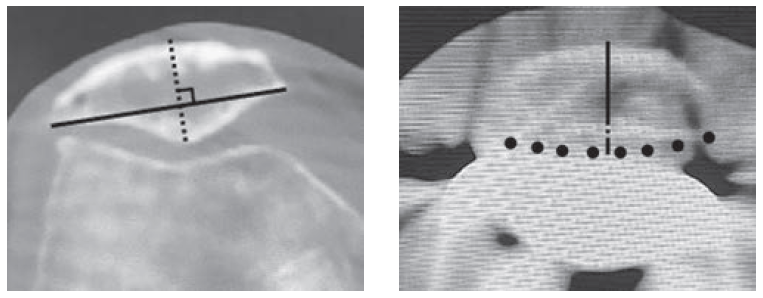

人工膝関節の手術(TKA)において、多くの患者様が懸念されるのが「術後の膝前面の痛み」です。深谷医師は自身の研究において、お皿の骨(膝蓋骨)の厚みが術前後でどう変化するかをミリ単位で検証しました。

• 研究の成果: インプラント設置後の厚みが術前と完全に一致(±0mm)するよう、専用の精密ガイド器具を用いた正確な骨切りと、余分な厚みを出さない高度なセメント固定技術を徹底。この「ミリ単位の再現性」へのこだわりは、現在のアレックスでの膝関節手術においても、違和感のないスムーズな動きを実現するための基盤となっています。